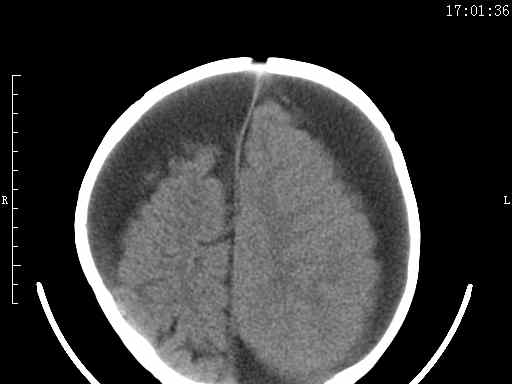

以下是引用余辉在2009-5-30 17:43:00的发言:[br]外围性脑积水在蛛网膜下腔,这个不像,双侧客部液区增宽,内见对称性弧形线状高密度影,边缘清晰锐利,右侧后端终止于冠状缝,左侧终止于人字缝,应该是硬脑膜.双侧硬膜下液区增宽,脑皮质受压变平,脑沟裂无显著增宽,考虑1双侧额颞顶部慢性硬膜外血肿伴硬膜下积液或慢性血肿2双侧慢性硬膜下积液伴硬脑膜剥离并有交通积液(反正考虑硬膜下及硬膜外的慢性血肿或积液)